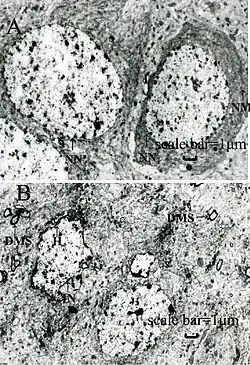

- dysfonctionnement des reins, avec augmentation de la prévalence de troubles rénaux[185] dès 15 µg/L de plombémie[186] (soit bien avant le seuil de 100 µg/L retenu pour la définition du saturnisme et retenue en France comme seuil de déclaration obligatoire et déclenchant la surveillance)[187] ; A échelle microscopique le plomb, même à faible dose dégrade les cellules du tube proximal du rein où apparaissent des inclusions intranucléaires, des inclusions intracytoplasmiques contenant du fer, et « de très importantes lésions mitochondriales » ; les inclusions intranucléaires induites par un saturnisme humain chronique présentent des aspects ultrastructuraux spécifiques et pouvant persister très longtemps après l'arrêt de l'intoxication (plus de dix ans dans un cas)[188] ;